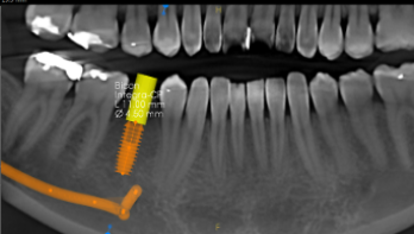

Implant planning

- Implant site measurements: first 3 implants FREE, then + $30/each